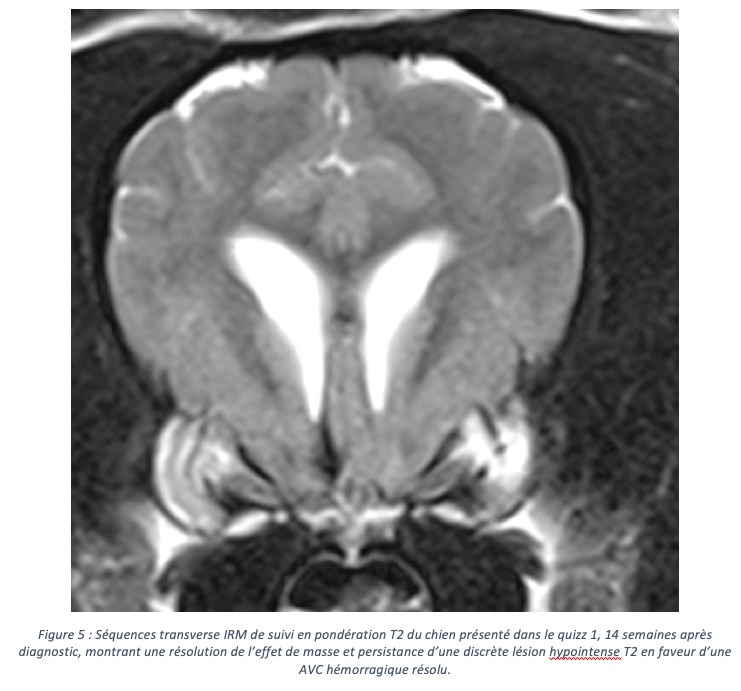

Savoir différencier un AVC d’une tumeur à l’imagerie

Quizz 1 : AVC hémorragique ou processus néoplasique sur ce chien de berger de 10 ans présenté pour des crises convulsives d’apparition aiguës ? Quizz 1 : la…